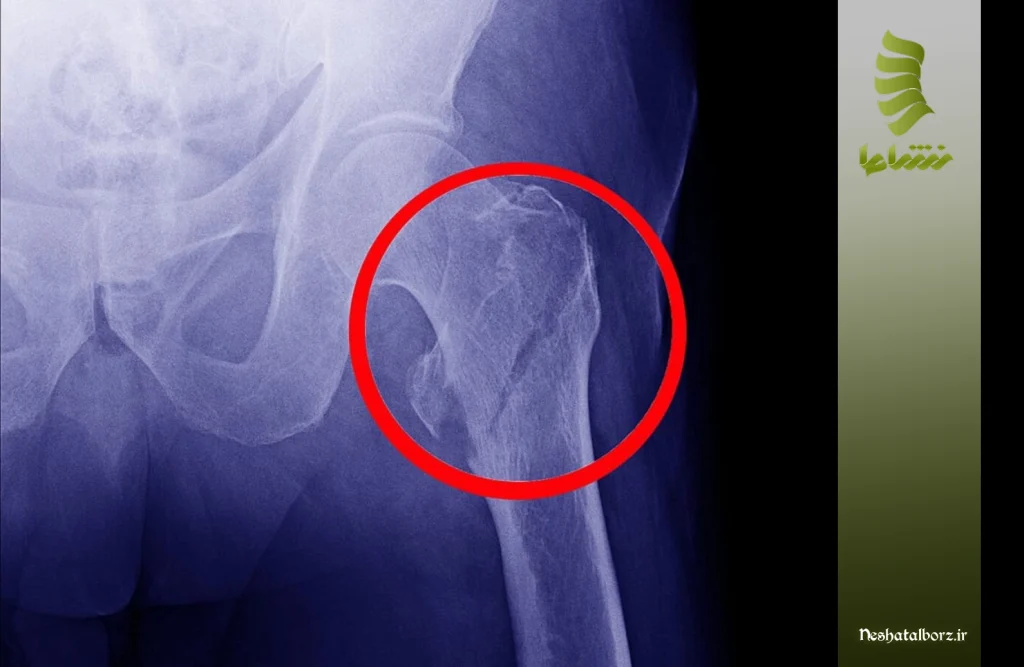

انواع شکستگی لگن

شکستگیهای لگن به طور کلی به دو گروه اصلی تقسیم میشوند: شکستگیهای مجموعه استابولوم (Acetabular Fractures) و شکستگیهای حفره لگن (Pelvic Ring Fractures). در ادامه توضیحاتی را درباره هرکدام ارائه دادهایم تا بیشتر با این عارضه آشنا شوید.

شکستگیهای استابولوم (Acetabular Fractures)

استابولوم یا حفره استابولار، بخشی از استخوان لگن است که سر استخوان ران (فمور) در آن قرار میگیرد و مفصل ران را تشکیل میدهد. شکستگی در این ناحیه اغلب به دلیل وارد آمدن نیروی مستقیم و شدید به لگن است (مانند تصادفات با سرعت بالا). این شکستگیها بر اساس الگوی شکستگی داخل حفره به دستههای مختلفی طبقهبندی میشوند (مانند انواع استایل یا مارکلوئیس). میزان جابجایی قطعات شکسته در استابولوم، اهمیت زیادی در تعیین روش درمانی دارد، زیرا هرگونه عدم انطباق (Mismatch) در سطح مفصلی میتواند به آرتروز زودرس در مفصل ران منجر شود.